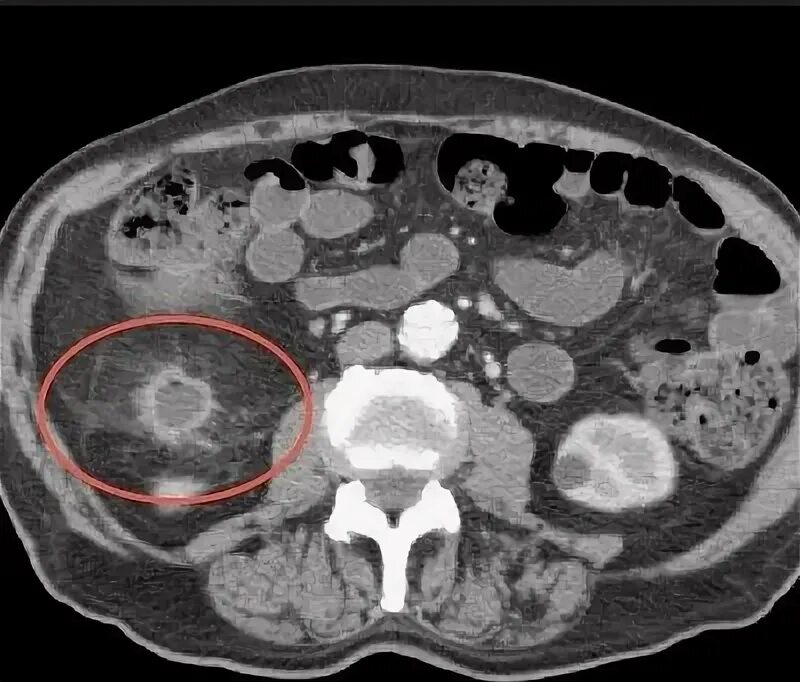

Как на кт выглядит рак